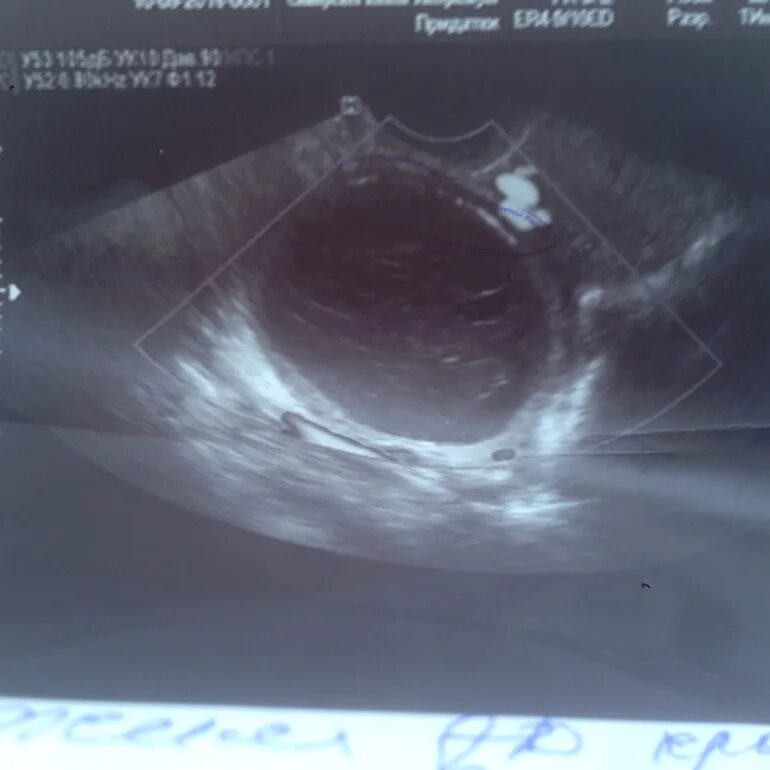

Фолликул после овуляции